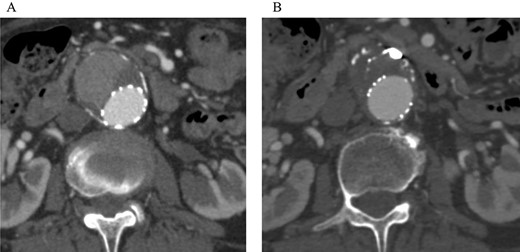

Angiography for decision-making revealed a type II endoleak from the IMA to the AAA, but no other visible endoleak (Fig. 2). Based on these findings, we planned additional EVAR for left CIAA, which was thought to have enlarged in natural course, and IMA embolization for the type II endoleak associated with sac enlargement. A staged strategy was devised. IMA embolization was planned several days after EVAR. Sac angiography from the IMA via Riolan’s arcade showed a flow-through endoleak to the ARA as a drainage artery (Fig. 3). Based on this finding, we embolized the ARA and the IMA with coils via Riolan’s arcade (Fig. 4). Selection and embolization of the drainage artery were technically feasible because of the flow from the IMA to the ARA. No deterioration of renal function due to ARA embolization was observed. One year after treatment, a CT scan demonstrated that the sac shrank to 42 mm with no evidence of a continuing endoleak (Fig. 5).

Post-embolization CT demonstrated that the sac shrank with no evidence of a continuing endoleak. (A) Pre-embolization CT showed a contrast effect in the sac. (B) Post-embolization CT showed no contrast effect in the sac.